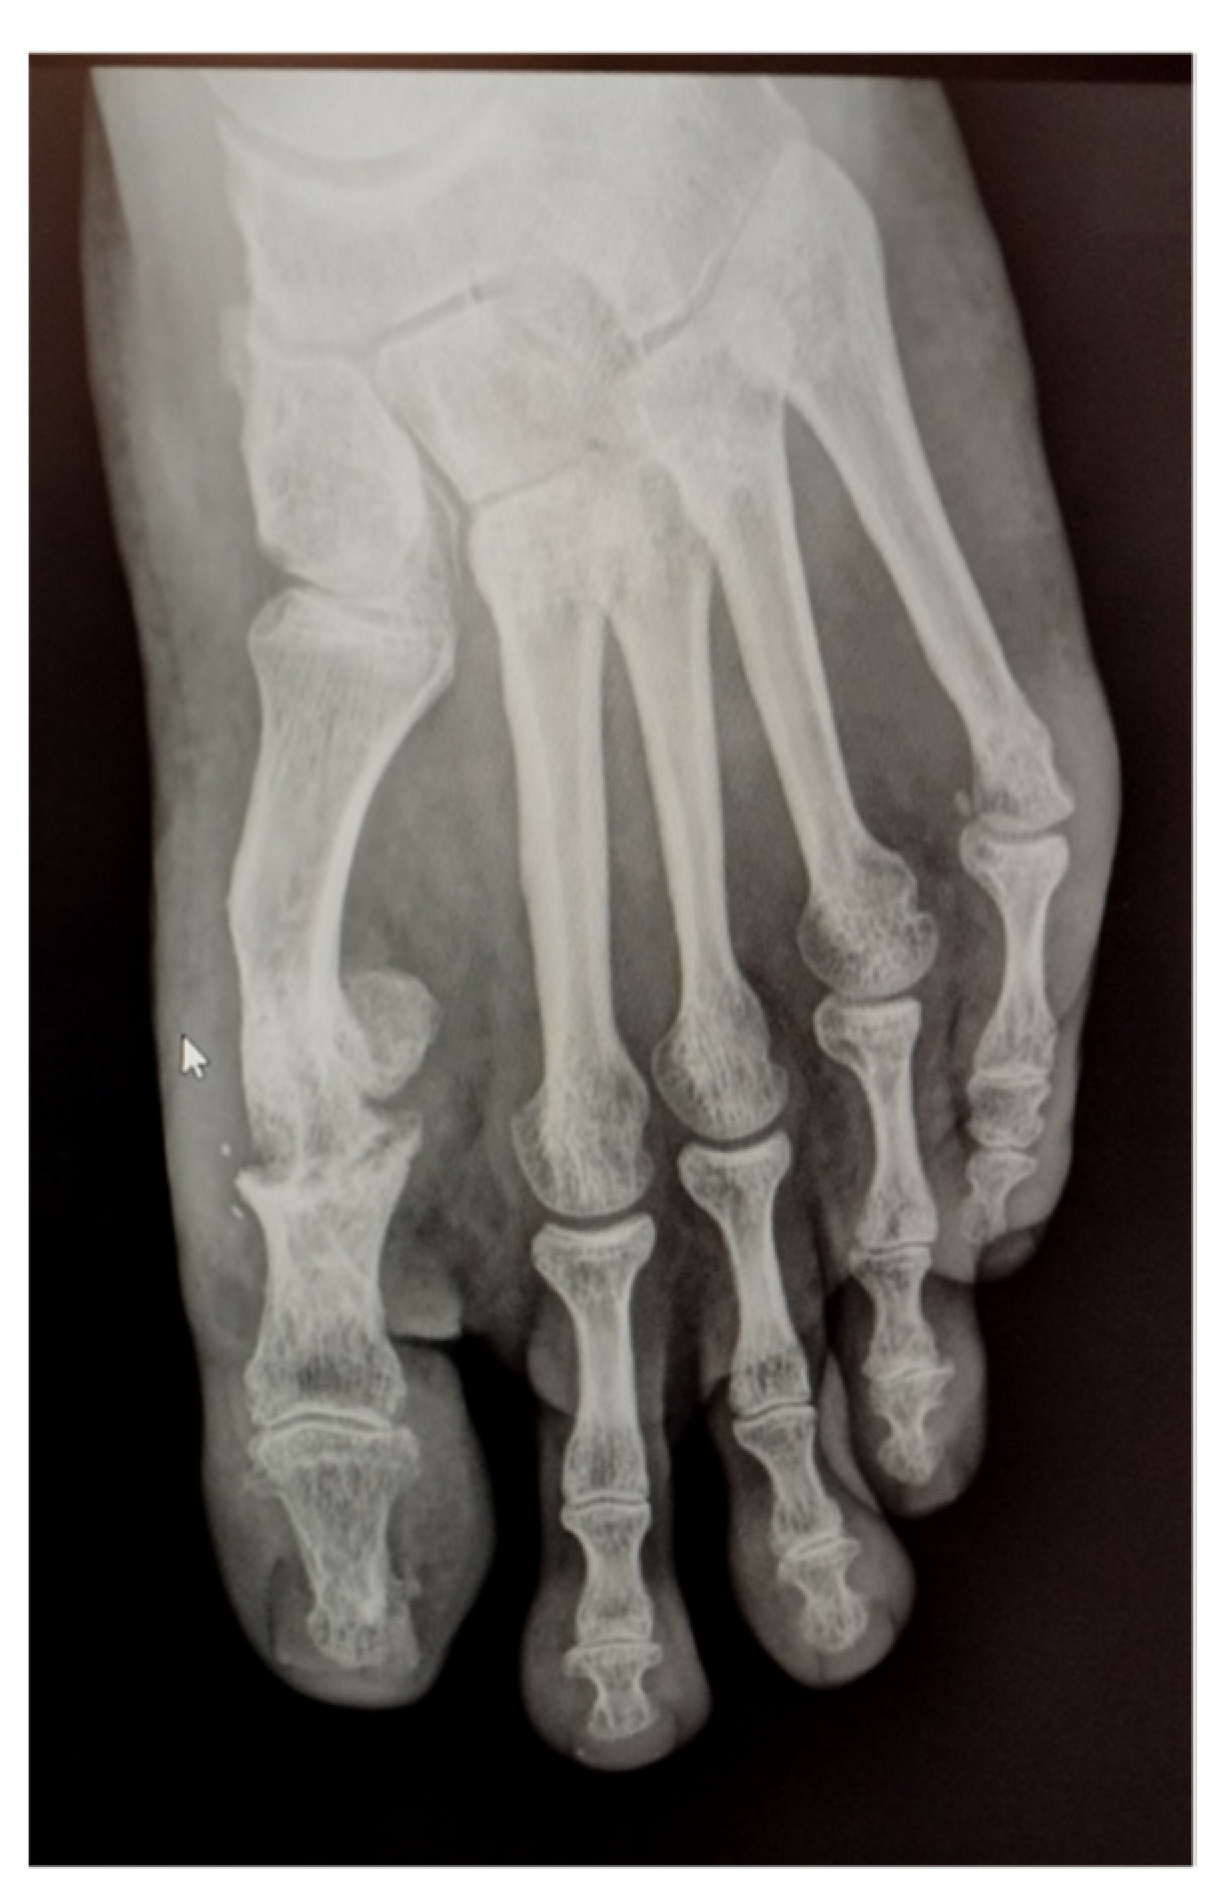

A 43-year-old man presented in surgical service of the Podiatric Clinic Area of the Universidad de Sevilla. He presented a painful matarso-phalangeal joint (MPJ) with loss of flexor capacity in the hallux and slight hyperesthesia in the tips of the hallux and in the second and third toes of the left foot. According to his surgical history, in 2021 he underwent an operation to correct hallux valgus deformity by chevron capital osteotomy and proximal Akin procedure (Figure 1). The patient reports that a year later he had to be operated on again due to pain at the level of the first MPJ to remove the osteosynthesis material. The second surgery was performed outpatiently with epidural anaesthesia through a medial incision at the level of the MPJ (Figure 2).

Figure 1. Radiological aspect of foot before of second procedure.